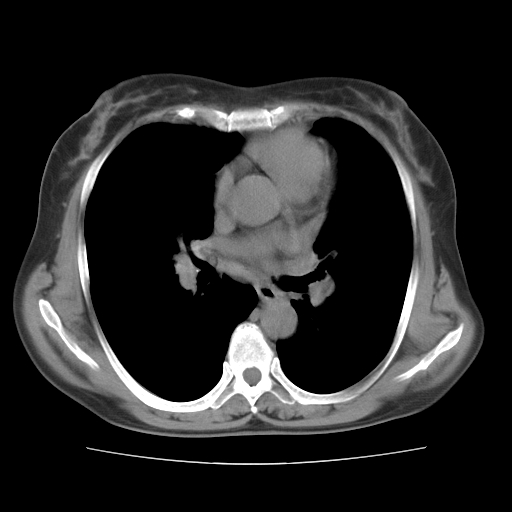

标题: CT10838:女性,56岁,是上腔静脉钙化还是淋巴结钙化?

女性,56岁临床诊断为胃贲门ca,术前检查发现,此钙化灶,对此科内稍有争论!请各位老师看看!是上腔的还是淋巴结的?有意义吗?

胸锁关节层面的是淋巴结钙化,气管前腔静脉后的钙化灶占了4个层面,不知层厚是多少?看样子应该是7--10毫米之间,那么这病灶最小纵径得有28毫米!应该提示点什么了,没传肺窗,估计肺内没有病变?

左锁骨下静脉和头臂静脉会合后形成是上腔静脉,此钙化位于两血管回合的腔静脉后方、气管右前方,这个位置没有其他结构,应该是淋巴结钙化。一般多为淋巴结核后钙化,没有临床意义。